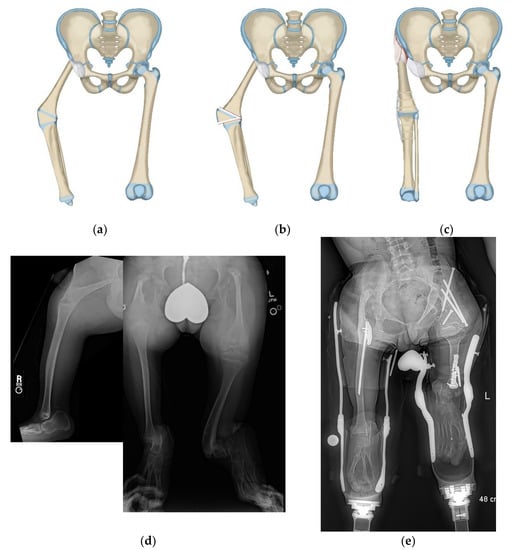

Figure 7.

(a) Illustration of CFD type 2c with congenital knee fusion with knee flexion deformity. The fibrous femoral neck anlage tethers the upper femur from migrating proximally. (b) Illustration showing the first step which is correction of knee flexion deformity with excision of distal femoral physis. (c) Illustration of the second step which is PaleySling–Van Nes rotationplasty. The rotationplasty is performed through the knee fusion site. The proximal femur is stabilized using the fascia lata by creating a sling around the proximal femur. The sling plus the fibrous neck anlage stabilize the upper femur from migrating proximally and while preserving the hip flexion-extension mobility (d) AP long radiograph (right) of a 14-year-old boy with bilateral CFD. The right side is classified as type 2c and also has a congenital knee fusion as seen on the long lateral radiograph (left). On the left side it is classified as a CFD type 3b and the knee joint is present and functional. (e) Standing long radiograph one year after bilateral rotationplasty performed in two separate surgeries. On the right side the rotationplasty was performed through the congenital knee fusion site together with a sling procedure at the hip (PaleySling–Van Nes). On the left side a Paley–Brown rotationplasty was performed together with a supramalleolar osteotomy for realignment.